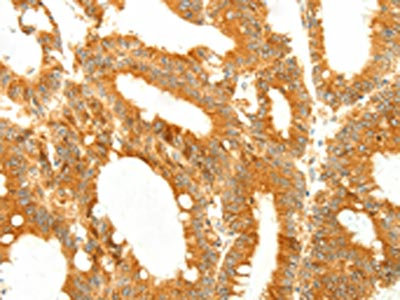

The image on the left is immunohistochemistry of paraffin-embedded Human colon cancer tissue using CSB-PA966330(DIABLO Antibody) at dilution 1/50, on the right is treated with fusion protein. (Original magnification: ×200)

The image on the left is immunohistochemistry of paraffin-embedded Human liver cancer tissue using CSB-PA966330(DIABLO Antibody) at dilution 1/50, on the right is treated with fusion protein. (Original magnification: ×200)